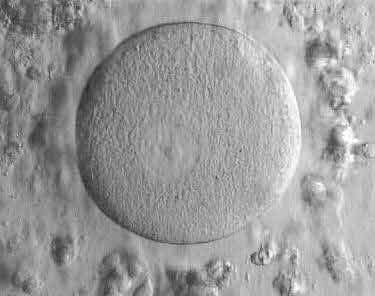

Which phase of cycle is this eggy at?

MII stage

(Zona pellucida + polar body)